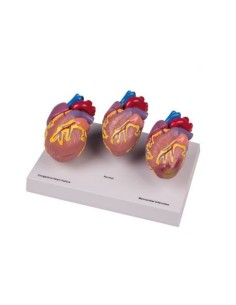

Du crâne en 22 parties à verrouillage magnétique aux modèles de colonne vertébrale, des modèles d'articulation aux modèles de cœur, chaque pièce de notre collection est conçue pour une immersion totale dans l'étude de l'anatomie humaine. Nos modèles, réalisés à partir de scans d'os réels, garantissent une expérience tactile authentique et une fidélité de poids presque identique aux originaux.